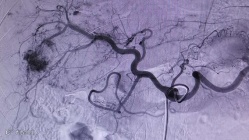

介入治疗:肝动脉介入栓塞术,具有创伤小、花费少、术后恢复快等优点,但复发率相对较高。